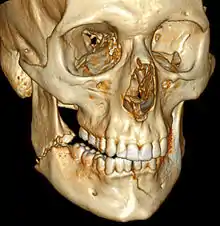

| 3D computed tomographic image of a mandible fracture in two places. One is a displaced right angle fracture and the other is a left parasymphyseal fracture. | |

Computed tomography

Computed tomography is the most sensitive and specific of the imaging techniques. The facial bones can be visualized as slices through the skeletal in either the axial, coronal or sagittal planes. Images can be reconstructed into a 3-dimensional view, to give a better sense of the displacement of various fragments. 3D reconstruction, however, can mask smaller fractures owing to volume averaging, scatter artifact and surrounding structures simply blocking the view of underlying areas.

3D CT reconstruction of mandible fracture, white arrow marks fracture, red arrow marks moderate displacement and open bite